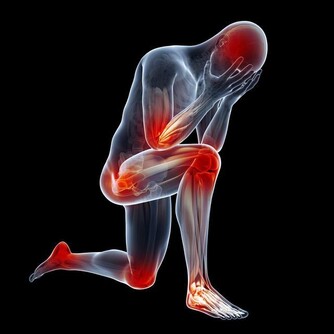

但實際上,鹼性磷酸鹽算是比較穩定的一類無機鹽,不是那種“輕佻的”、稍有“風吹草動”就會“改變立場”的物質。

常吃酸味食物,會影響骨骼發育,讓孩子長不高? 父母都該了解下

更重要的是,酸性食物被人體攝入後,並不是直接和骨骼接觸的,它要經過消化系統的消化吸收。

消化系統會根據體液的酸鹼情況,對營養物質進行“擇優錄取”——急需的、缺少的多吸收,反之則少吸收。

除此之外,人體的腎臟還是體內最重要的酸鹼平衡器官。

在腎功能正常的情況下,體內液體的酸鹼度將會維持在一個非常穩定的狀態(7.35~7.45)。體內酸多了,腎臟就會多排出酸,反之亦然。

這種非常穩定的酸鹼度,是不可能引起大量鹼性磷酸鈣鹽溶解這種“軒然大波”的。

可見,經常吃酸性食物,並不會引起骨骼內礦物質的溶解流失,更不存在影響長個子一說。